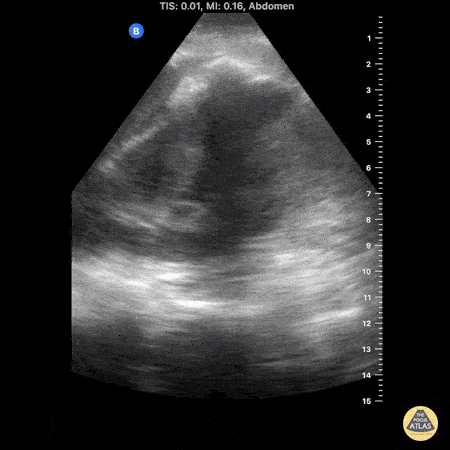

Renal/GU - Perinephric Abscess

Patient was admitted to ICU for DKA + pyelonephritis + E. Coli bacteremia. She was treated in the ICU and downgraded to the medicine floors, after tx for septic shock, but had persistent leukocytosis and intermittent LUQ px. Repeat CT showed 2.2 x 3.5 x 3.9 cm perinephric abscess, with the following images taken after identification on CT. 8cc of purulent drainage was subsequently drained via IR. Shane Solger, MD King's County/SUNY Downstate